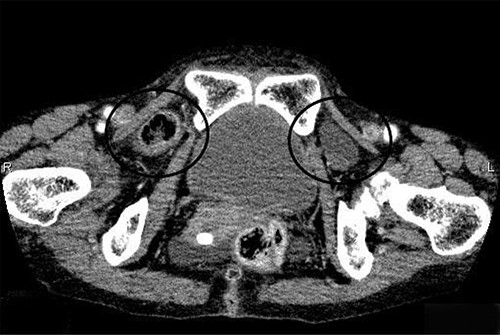

The patient was a 74-year-old woman who presented to our institution with nausea and abdominal distension. She had a history of restrictive lung disease, pulmonary hypertension, and appendicitis. Her height was 161 cm and weight 34.4 kg. She had a body mass index of 13.8 kg/m2. Physical examinations revealed abdominal distension and mild tenderness in the lower abdomen but no apparent signs of peritonitis. C-reactive protein was mildly elevated at 1.15 mg/dl, while the other laboratory blood test parameters were normal. An abdominal computed tomography (CT) demonstrated that the small intestine was incarcerated in the right obturator foramen and showed intestinal obstruction. A part of the bladder was impacted in the left OH (Fig. 1). A manual reduction of the incarcerated right OH was performed under ultrasound (US) guidance because there were no apparent necrotic bowel findings. Elective surgery was subsequently performed.

Abdominal CT scan revealed that the small bowel was incarcerated in the right obturator foramen and part of the bladder was impacted in the left obturator foramen.